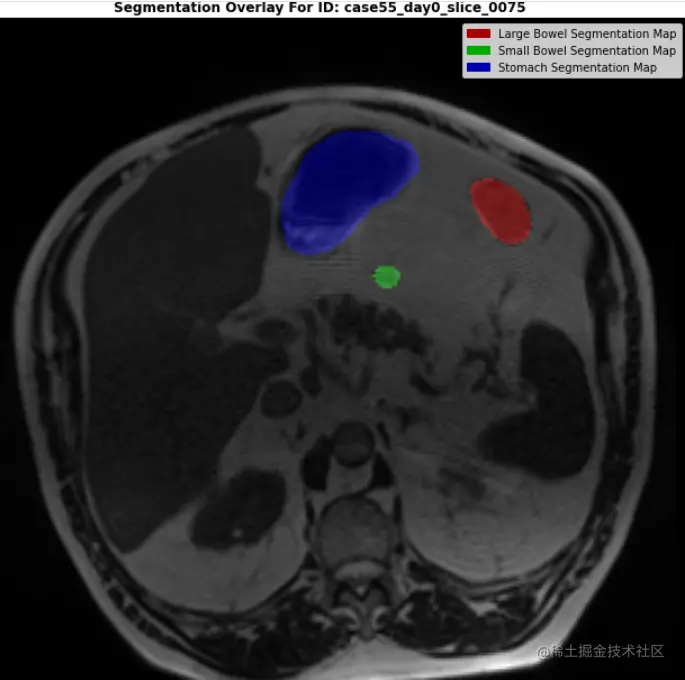

DEMO_ID = "case123_day20_slice_0082"

print(f"\n\n... LET'S PLOT THE IMAGE WITH AN RGB SEGMENTATION MASK OVERLAY ...\n")

plt.title(f"Segmentation Overlay For ID: {demo_ex.id}", fontweight="bold")

handles = [Rectangle((0,0),1,1, color=_c) for _c in [(0.667,0.0,0.0), (0.0,0.667,0.0), (0.0,0.0,0.667)]]

labels = ["Large Bowel Segmentation Map""Small Bowel Segmentation Map""Stomach Segmentation Map"]

plt.legend(handles,labels)

plt.axis(False)

plt.show()